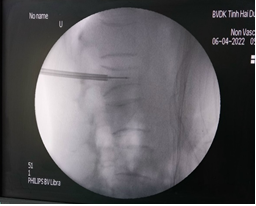

Bước 1: Xác định điểm vào thân đốt sống tổn thương thông qua cuống trên C-arm

Bước 2: Tiến hành sát trùng và gây tê tại vùng chọc kim gần với tổn thương nhất.

Bước 3: Tiến hành bơm thuốc cản quang để đánh giá, kiểm tra thành đốt sống có toàn vẹn hay không.

Bước 5: Đây là bước quan trọng nhất khi thực hiện kỹ thuật, xi măng sinh học sẽ được bơm qua kim định vị rỗng rỗng vào thân đốt sống bị xẹp. Tốc độ bơm phải chậm và được theo dõi chặt chẽ của bác sĩ thông qua C-arm và những biểu hiện lâm sàng của bệnh nhân như tình trạng đau hay cử động hai chân.